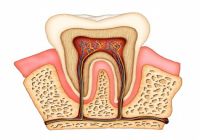

Endodontics

Also known as Root Canal Therapy, this is a process where a tooth is infected or abscessed due to decay or trauma. The nerve can be removed to save the natural tooth. |